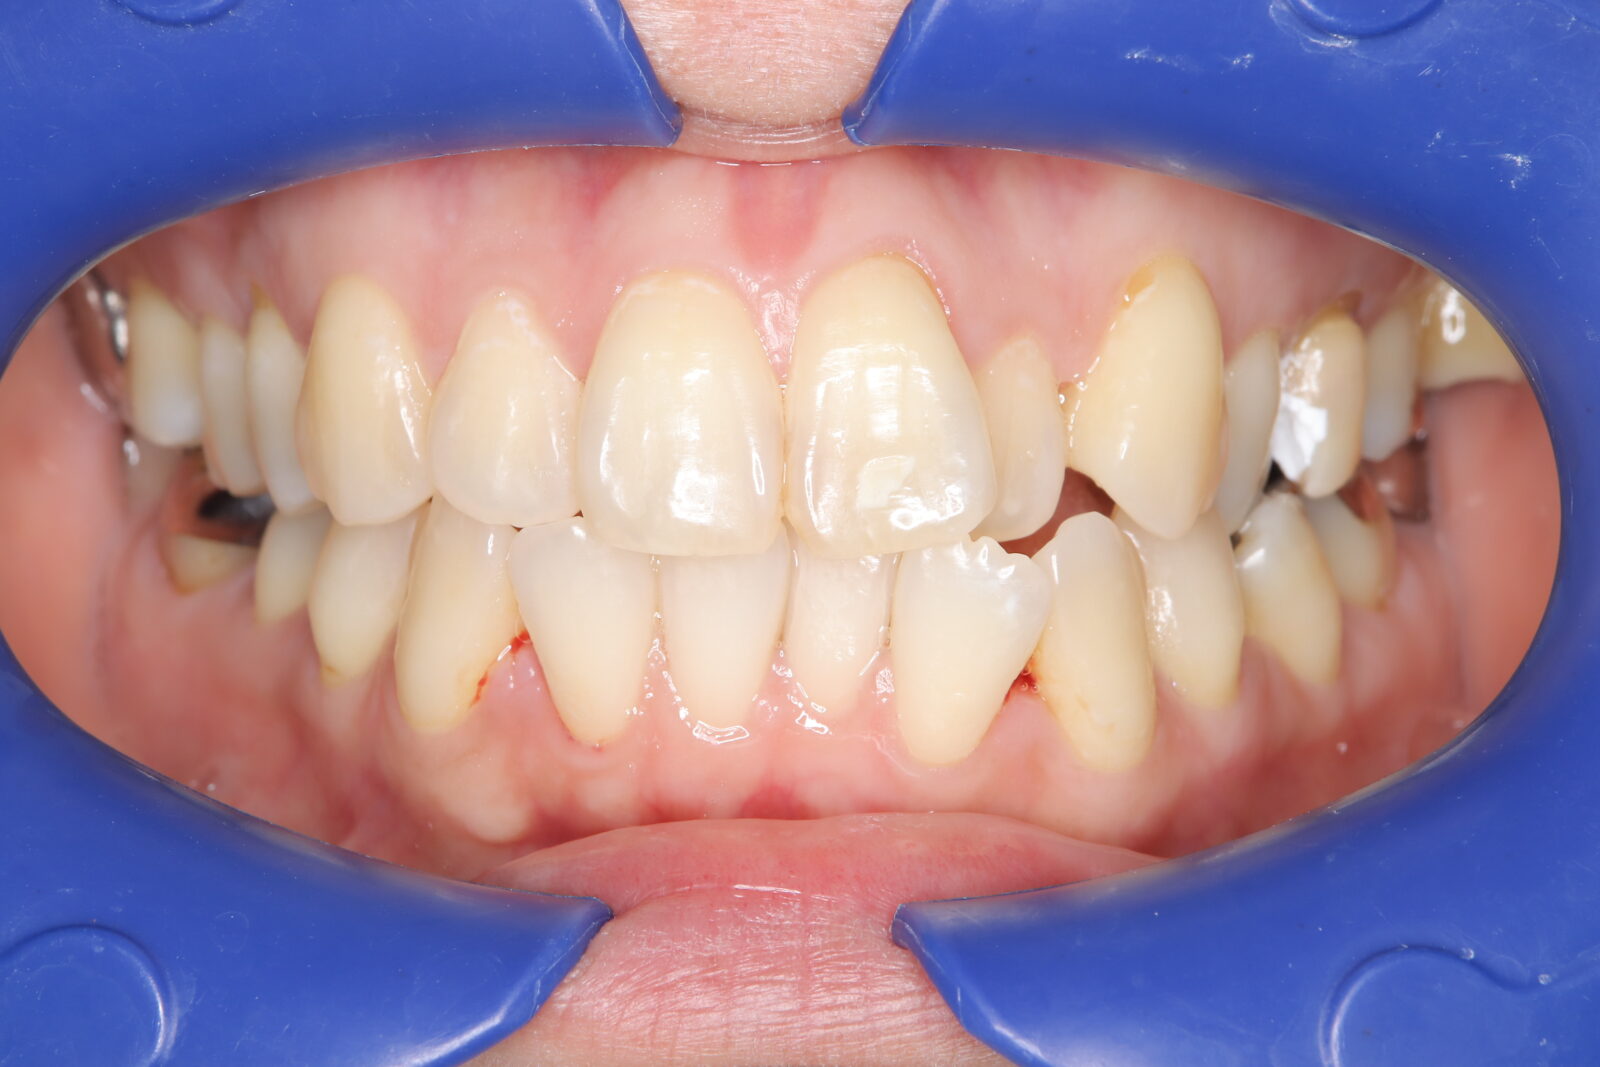

インビザライン(全体矯正)+ホワイトニングコースの症例

上下の前歯の歪みと奥歯のすれ違いをインビザライン(全体矯正)とホワイトニングで綺麗に矯正。

・費用:935,000円(税込)

・治療期間:30ヶ月

・通院回数:30回

・31歳女性